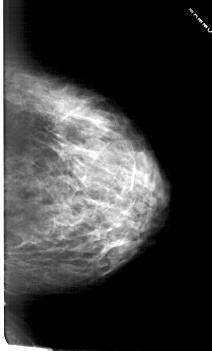

A_1814_1.LEFT_CC

LEFT_CC LINES 6451 PIXELS_PER_LINE 3496 BITS_PER_PIXEL 12 RESOLUTION 43.5 OVERLAY

FILE: A_1814_1.LEFT_CC.OVERLAY

TOTAL_ABNORMALITIES 1

ABNORMALITY 1

LESION_TYPE MASS SHAPE OVAL MARGINS CIRCUMSCRIBED

ASSESSMENT 3

SUBTLETY 3

PATHOLOGY BENIGN

TOTAL_OUTLINES 1

BOUNDARY